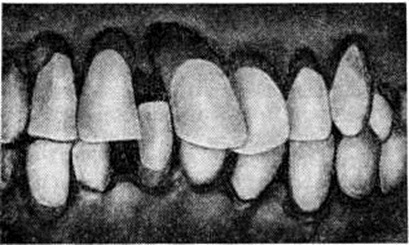

Рис. 3.

Внешний вид зубов при пародонтозе: зубы смещены и повёрнуты по оси, корни их обнажены.

Развившаяся стадия Пародонтоз, как правило, характеризуется наличием генерализованного гингивита, пастозностью дёсен с явлениями застойной гиперемии, их кровоточивостью, наличием пародонтальных карманов глубиной 5—6 миллиметров и более, в большинстве случаев с выделением из них гноя. Отмечается обильное отложение плотного поддесневого камня, который в отличие от наддесневого проникает в глубь пародонтальных карманов в виде тонких зернистых наслоений, плотно прикрепляющихся к корням зубов. Зубы становятся подвижными, часто смещаются, поворачиваются по оси (рисунок 3), выпадают. Между зубами, ранее плотно соприкасавшимися, образуются свободные промежутки (смотри полный свод знаний: Диастема, Трема). Подвижные зубы травмируют окружающие ткани и усиливают воспаление. При обнажении шеек и корней зубов открытые их зоны подвергаются длительному раздражению при приёме пищи, вдыхании охлаждённого воздуха, разговоре и становятся источником болей. Отмечаются смещение зубов, нарушение дикции, у некоторых больных появляется неприятный запах изо рта. Общее состояние, как правило, страдает незначительно, иногда отмечается субфебрильная температура. Но в ряде случаев состояние больных резко ухудшается.